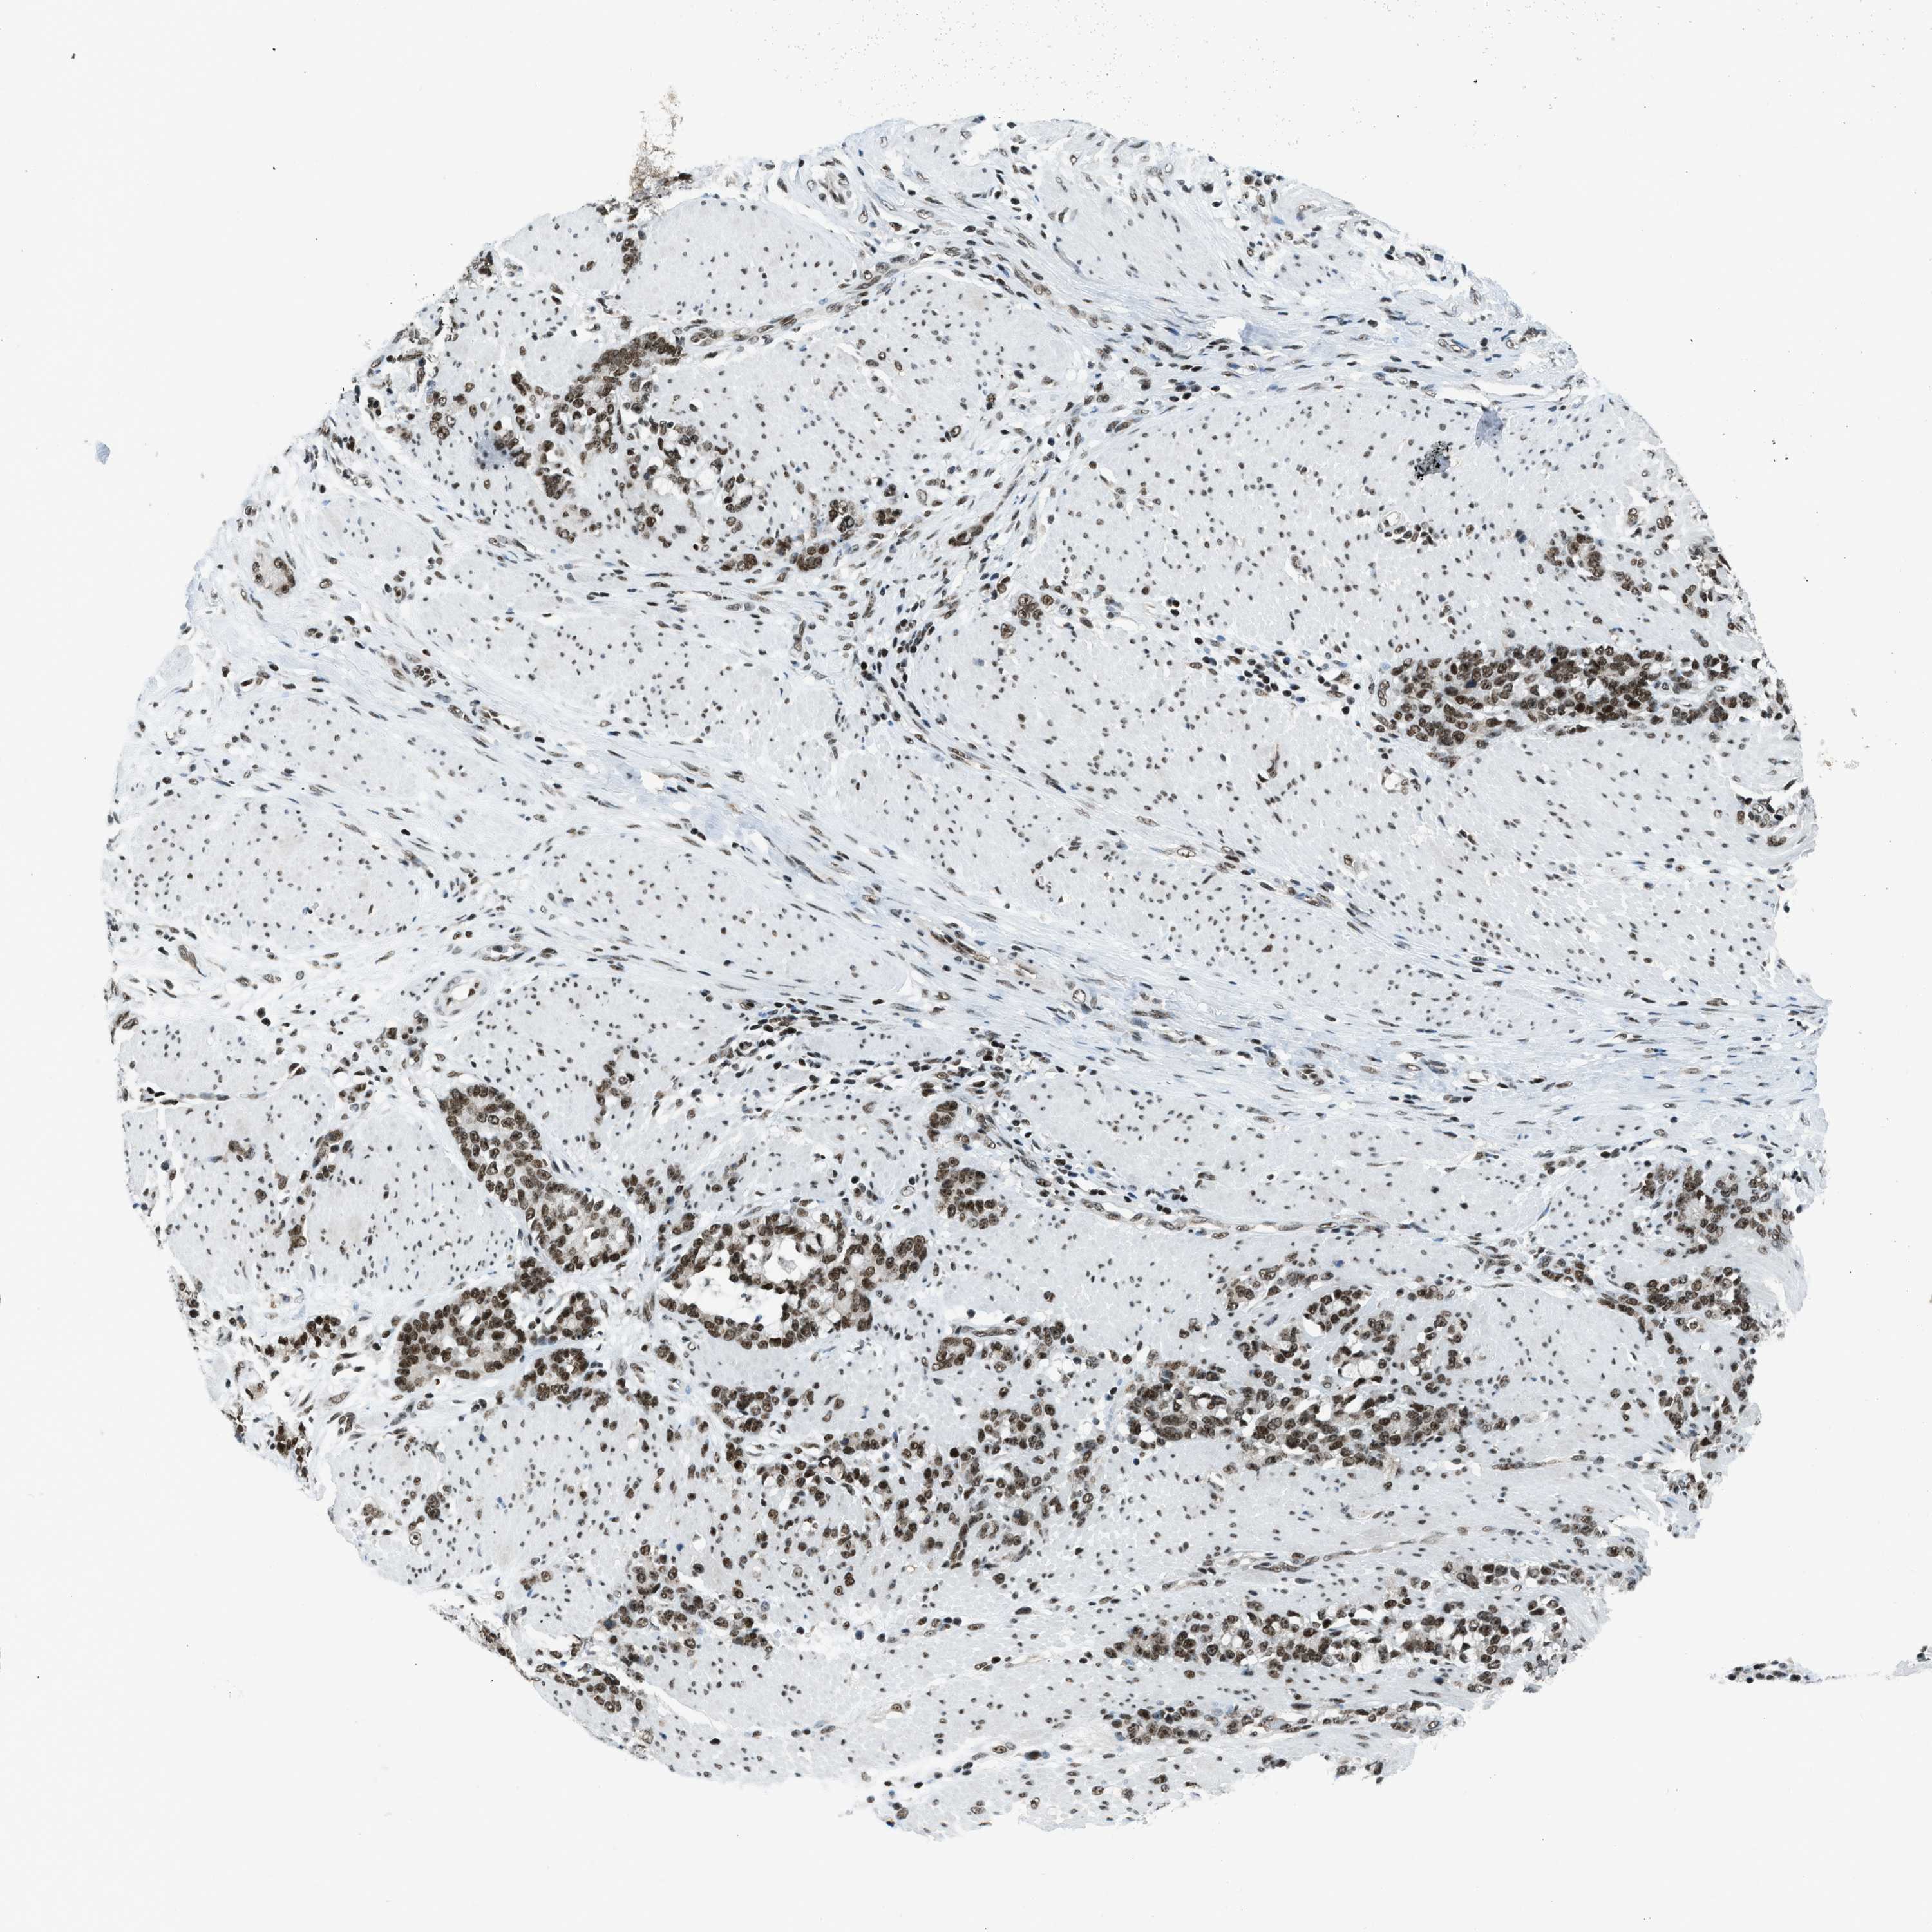

STOMACH CANCER - Protein expressioni

A mouse-over function shows sample information and annotation data. Click on an image to view it in a full screen mode. Samples can be filtered based on level of antibody staining by selecting one or several of the following categories: high, medium, low and not detected. The assay and annotation is described here.

Note that samples used for immunohistochemistry by the Human Protein Atlas do not correspond to samples in the TCGA dataset.

Antibody stainingi

Antibody staining in the annotated cell types in the current human tissue is reported as not detected, low, medium, or high, based on conventional immunohistochemistry profiling in selected tissues. This score is based on the combination of the staining intensity and fraction of stained cells.

Each image is clickable and will lead to virtual microscopy that enables deeper exploration of all samples and also displays staining intensity scores, fraction scores and subcellular localization as well as patient and tissue information for each sample.

Antibody CAB016191

Staining

High

Medium

Low

Not detected

Intensity

Strong

Moderate

Weak

Negative

Quantity

>75%

75%-25%

<25%

None

Location

Nuclear

Cytoplasmic/membranous

Cytoplasmic/membranous,nuclear

Adenocarcinoma, NOS

Adenocarcinoma, High grade